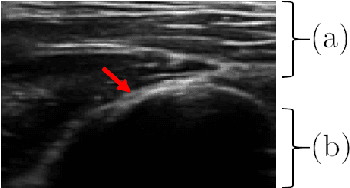

Abstract:Bone surface delineation in ultrasound is of interest due to its potential in diagnosis, surgical planning, and post-operative follow-up in orthopedics, as well as the potential of using bones as anatomical landmarks in surgical navigation. We herein propose a method to encode the physics of ultrasound propagation into a factor graph formulation for the purpose of bone surface delineation. In this graph structure, unary node potentials encode the local likelihood for being a soft tissue or acoustic-shadow (behind bone surface) region, both learned through image descriptors. Pair-wise edge potentials encode ultrasound propagation constraints of bone surfaces given their large acoustic-impedance difference. We evaluate the proposed method in comparison with four earlier approaches, on in-vivo ultrasound images collected from dorsal and volar views of the forearm. The proposed method achieves an average root-mean-square error and symmetric Hausdorff distance of 0.28mm and 1.78mm, respectively. It detects 99.9% of the annotated bone surfaces with a mean scanline error (distance to annotations) of 0.39mm.